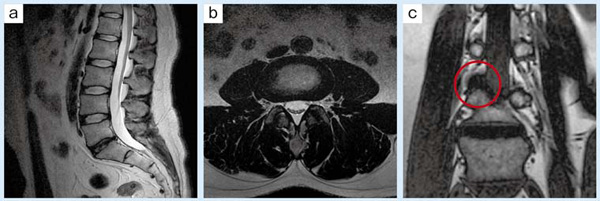

■症例3:腰椎外側ヘルニア

41歳,男性。腰椎ルーチン検査で異常所見がみつからない場合でも(a,b),症状からヘルニアが疑われる場合は,神経根の走行に沿うように椎体後面から5°〜10°傾けたT1強調コロナル像を追加で撮像している(c)。神経根を圧排する外側ヘルニアが判明する症例が時々見られる(○)。

a:T2WI,SAG,FOV:300mm,TR/TE:3500/104,FA:90°,スライス厚:4mm

b:T2WI,AX,FOV:180mm,TR/TE:3300/108,FA:90°,スライス厚:4mm

c:T1WI,COR,FOV:300mm,TR/TE:450/11,FA:90°,スライス厚:3mm